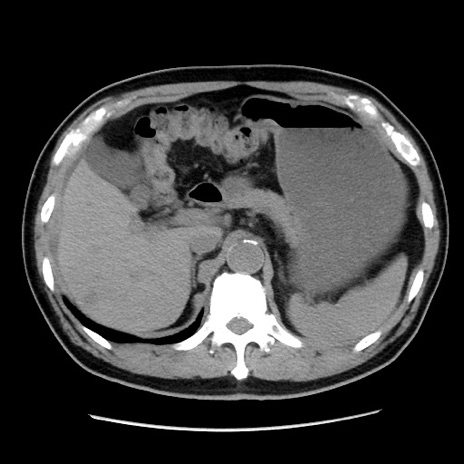

症例16(横断像)

【症例】 70歳代男性

【主訴】 腹痛、嘔吐

【現病歴】 約1ヶ月前より間欠的に腹痛と嘔吐あり、当院消化器内科を受診したところCTで多発する肝臓のLDAを指摘され、精査中であった。以降は消化器症状は安定していたが、2日前より嘔気と腹痛があり、同日より排便・排ガスが消失した。改善認めず、 本日、救急外来を受診した。

【既往歴】 大腸ポリープ切除後。

【身体所見】意識清明・会話良好、BT 36.3℃、BP 127/80mmHg、 P 80bpm、腹部:膨満あり、平坦・軟、上腹部正中および下腹部正中に圧痛あり、反跳痛なし、筋性防御なし。

【データ】WBC 7200、CRP 0.77